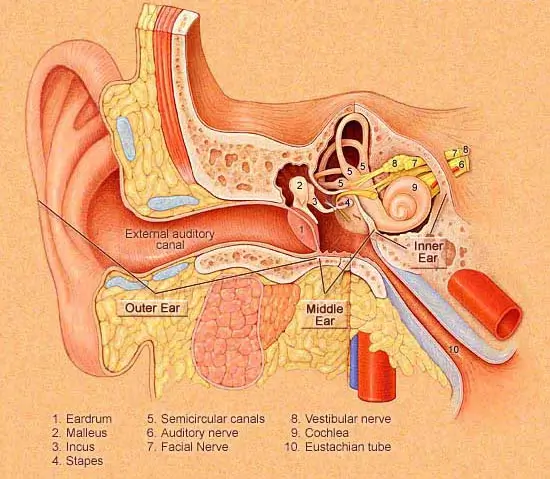

- Sound travels through the outer, middle, and inner ear

- The eardrum vibrates in response to sound waves

- Tiny bones amplify vibrations to the inner ear

- Signals are sent to the brain via the auditory nerve

Conductive hearing loss happens when sound is unable to pass through the outer ear, ear canal, or middle ear to reach the inner ear. It may be caused by infections, fluid buildup, a perforated eardrum, or structural issues. This condition reduces sound volume, making soft or distant sounds harder to hear — but clarity remains unaffected

Sensorineural hearing loss happens due to damage in the inner ear (cochlea) or the auditory nerve pathways that carry sound to the brain.